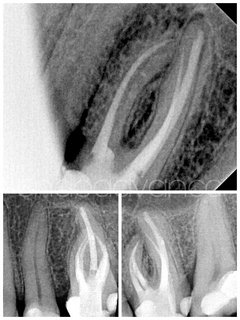

Αρχική ενδοδοντική θεραπεία σε 2ο κάτω γομφίο με μορφολογία C-shaped